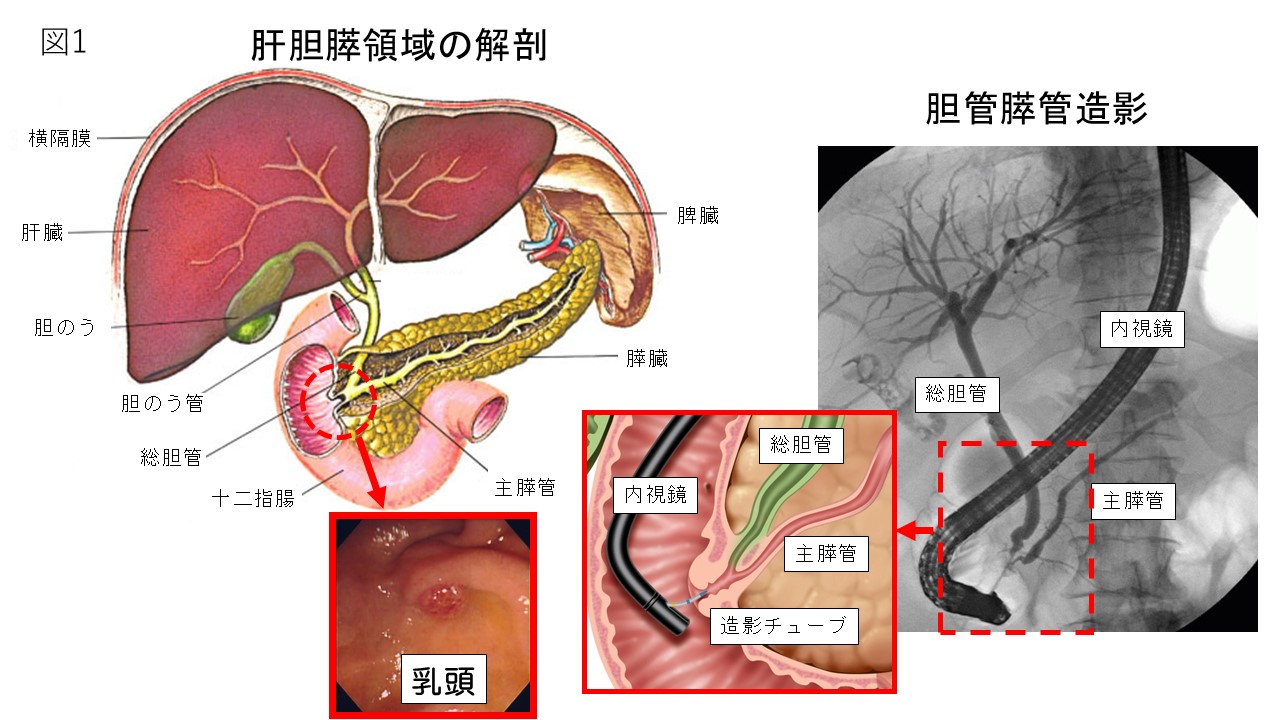

胆膵内視鏡の診断・治療の基本手技 第3版 | 糸井 隆夫 |本。胆膵内視鏡 診断・治療の基本手技 第4版 | 糸井 隆夫 |本 | 通販。胆膵内視鏡の診断・治療の基本手技 第3版 | 糸井 隆夫 |本。国産米粉のホットケーキミックス☆驚くほどもっちり☆MOLINAGA☆2袋セット。胆膵内視鏡 診断・治療の基本手技 第4版 - 羊土社。最先端治療 胆道がん・膵臓がん – 法研。裁断済(バラバラ)の本です。胆膵内視鏡の診断・治療の基本手技 第3版 - 羊土社。。胆膵内視鏡 診断・治療の基本手技 第4版 - 羊土社。胆膵内視鏡でサポートバンドを導入 - 事例紹介|Medicle。内視鏡センター|社会医療法人三栄会 ツカザキ病院。胆膵内視鏡の診断・治療の基本手技 改訂2版」付録DVD。胆膵内視鏡の診断・治療の基本手技 - 羊土社。裁断済みの為、状態が悪いとしていますが、書き込み等ございません。使い方の分かる方のご購入をお願いいたします。JDDWで売上1位を獲得した話題の新刊『これで完璧!胆膵内視鏡の